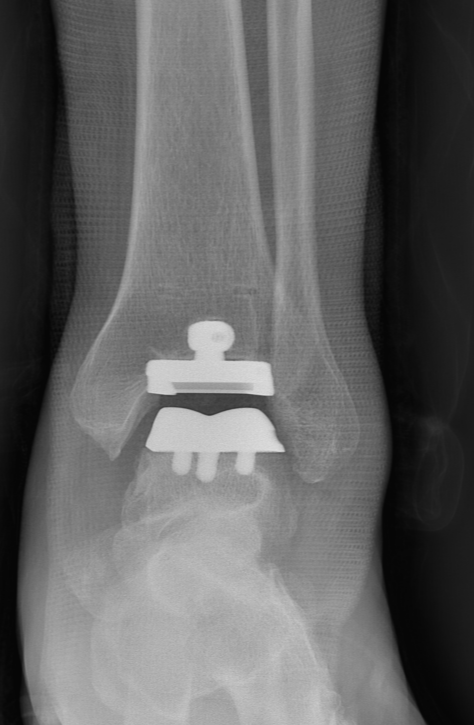

第一台手术的患者是位75岁的叔叔,被“脚脖子”痛缠了4年,疼得越来越厉害,病情已经到了严重阶段。

武勇主任团队给他做了3D打印导板辅助下人工全踝关节置换术。

这种手术适合踝关节病严重的患者,通过替换病变的关节结构,能帮着缓解疼痛、恢复关节活动,让老人日常走路更自在些。

术后侧位X线

术后正位X线